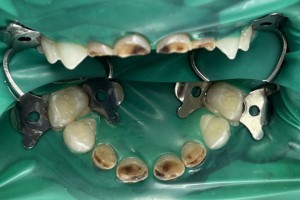

Семейная областная стоматология "Кидди Дентал" - это команда компетентных врачей, каждый из которых знает и любит свое дело. Опыт наших врачей, использование современного оборудования и надежных материалов позволят проводить лечение любой сложности.